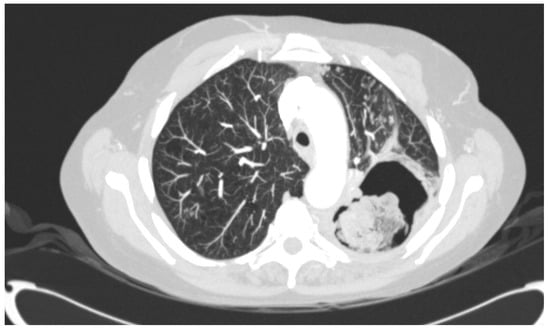

Figure 1.

Chest computed tomography image showing a large pulmonary cavity in the left upper lobe with a mass lying in the cavity.